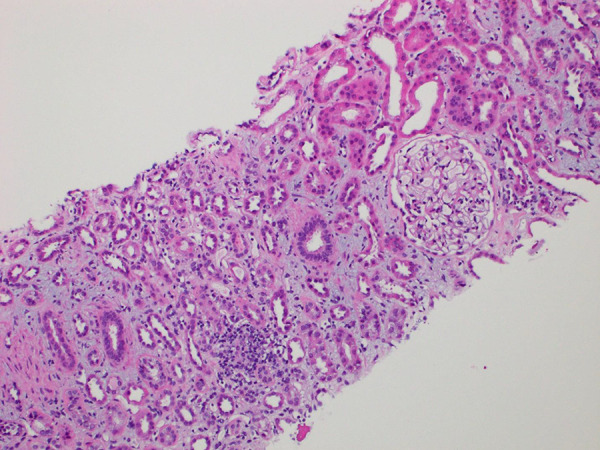

急性间质性肾炎(AIN)是医院获得性急性肾损伤(AKI)的常见病因[1]。AIN最常见的病因是药物诱发的AIN,占60-70%的病例[2]。阿利昔单抗(PCSK9 抑制剂)是一种单克隆抗体,通过抑制 PCSK9 蛋白降低低密度脂蛋白-C 水平[3]。阿利库单抗常见的不良反应包括注射部位反应、肌痛、神经认知障碍和眼科疾病 [4]。有关阿利珠单抗引起急性肾小管坏死(ATN)的病例报道较少,且多以急性肾小管坏死的形式出现[5]。本文介绍了一例与阿利珠单抗使用相关的 AIN 新病例。

Acute interstitial nephritis (AIN) is a common cause of hospital-acquired acute kidney injury (AKI) [1]. The most common cause of AIN is drug-induced AIN, which accounts for 60 - 70% of cases [2]. Alirocumab, a proprotein convertase subtilisin/kexin type 9 inhibitor (PCSK9 inhibitor) is a monoclonal antibody that lowers low-density lipoprotein-C levels by inhibiting the PCSK9 protein [3]. Common adverse events reported with alirocumab include injection-site reactions, myalgia, neurocognitive disorders, and ophthalmologic disorders [4]. There is paucity of data, with few reported cases of AKI, mostly in the form of acute tubular necrosis (ATN) associated with alirocumab [5]. In this article, we present a novel case of AIN associated with the use of alirocumab.